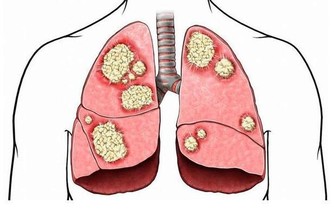

同時大白菜中還含有微量元素硒-是心臟代謝不可獲缺的微量元素,被譽為『生命火種』。

如果人體缺硒,就好象失去了一道抵抗癌癥的堅固防線。硒也是人體一種重要的過氧化酶的組成部分,這種酶不僅可以防止不飽和脂肪酸的氧化,還能夠抑製可能成為致癌過氧化物和遊離基的形成。

科學家們認為,硒通過吞噬細胞的功能、能夠影響癌細胞的能量代謝、和幹擾癌細胞的蛋白合成,從而抑製癌癥,還能夠影響化學致癌物的代謝,使它們失去致癌的活性。

大白菜中含有的微量元素鐵、也是飲食中防癌、抗癌的一種重要的成份!